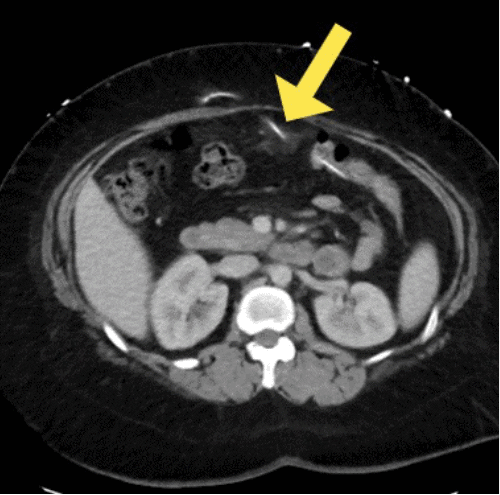

She initially presented to the emergency department twice within a two-week period. The initial presentation was for intractable headaches. A head computed tomography (CT) ruled out hydrocephalus, and an X-ray shunt series showed an intact VP shunt catheter (Figure 1). Despite these findings, she was discharged home after two days. However, headaches persisted upon discharge, accompanied by new symptoms of epigastric abdominal pain and diarrhea. The night prior to presentation, triggered by the sensation of something protruding from her anus during a bowel movement, physical examination revealed a tender epigastric region but no signs of peritonitis or meningitis. The examination also identified the peritoneal end of the VP shunt visibly protruding through the anus, as seen in Figure 2.

Figure 1. VP Shunt Series Demonstrating Appropriate Catheter Position. Published with Permission

A CT scan of the abdomen and pelvis revealed the VP shunt entering the lumen of the distal transverse colon extending distally to the level of the rectum. There were inflammatory changes noted at the anterior mid-abdomen surrounding the catheter, but no intraperitoneal air, ascites, or adenopathy. A representative image of the CT scan is shown in Figure 3.

Figure 3. Axial CT Scan of Abdomen Demonstrating Protrusion of VP Catheter Through Transverse Colon. Published with Permission

While physical examination showing the VP catheter protruding is often diagnostic, various imaging modalities can be used as supplemental tools. Abdominal X-rays, CT scans, and endoscopy have all been described as helpful adjuncts in the diagnosis.4 However, studies by Shuiab et al. have highlighted the low diagnostic yield of the VP shunt X-ray series in detecting clinically significant shunt malfunctions. Their research found a low sensitivity (18.7%) and positive predictive value (13%) for this modality.17 The authors concluded that using this diagnostic modality prolonged turnaround time, increased medical costs, and unnecessary radiation exposure for patients. Utilizing the patient's symptomology and CT scans should be the preferred diagnostic modality.17 Notably, in our case, a VP shunt series performed two weeks prior to presentation failed to identify the complication.